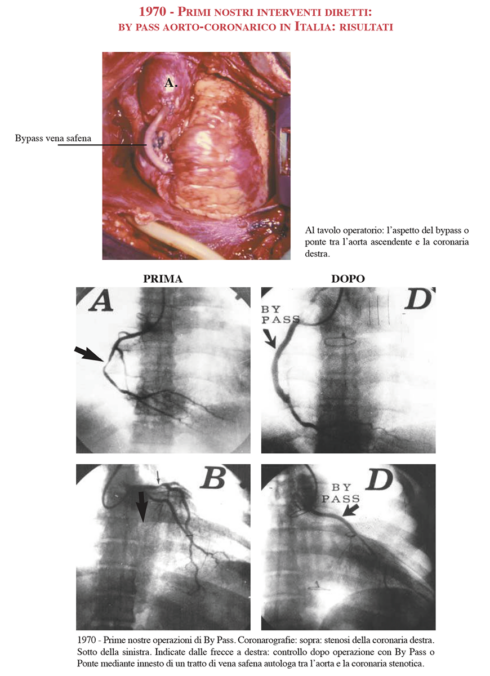

“Era un medico umanissimo. Era instancabile – continua Guglielmo –. Eseguì negli anni oltre 32mila interventi, un numero impressionante! Ai tempi si operavano anche venti e più pazienti al giorno. E mentre Dogliotti fu il primo al mondo a perfezionare l’applicazione della macchina cuore-polmone per la circolazione extracorporea, mio padre, insieme a Pier Federico Angelino, eseguì il primo cateterismo cardiaco in Italia”.

Come è documentato nel libro “Opera di Angelo Actis Dato. Cinquant’anni di cardiochirurgia” pubblicato nel 2002 da Minerva Medica Edizioni, Angelo Actis Dato è annoverato nelle cronache sanitarie quale ideatore di una serie innumerevole di brevetti.